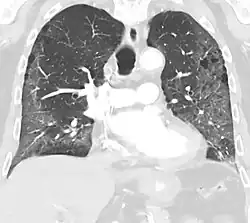

CT image in patient with COVID-19 showing bilateral ground-glass opacities at the periphery of both lungs.

Ground-glass opacity is among the most common imaging findings in patients with confirmed COVID-19.[16][17] One systematic review found that among patients with COVID-19 and abnormal lung findings on CT, greater than 80% had GGOs, with greater than 50% having mixed GGOs and consolidation.[16] GGOs with mixed consolidation has most often been found in elderly populations.[18] Several studies have described a pattern among initial, intermediate, and hospital discharge imaging findings in the disease course of COVID-19. Most commonly, initial CT imaging reveals bilateral GGOs at the periphery of the lungs. During initial stages, this is most often found in the lower lobes, although involvement of the upper lobes and right middle lobe has also been reported early in the disease course.[16][18] This is in contrast to the two similar coronaviruses, SARS and MERS, which more commonly involve only one lung on initial imaging.[19][20] As the COVID-19 infection progresses, GGOs typically become more diffuse and often progress to consolidation.[11][18] This is sometimes accompanied by the development of a crazy paving pattern and interlobular septal thickening.[18] In many cases the most severe pulmonary CT abnormalities occurred within 2 weeks after symptoms began.[17] At this point, many individuals begin showing resolution of consolidation and GGOs as symptoms improve. However, some patients have worsening symptoms and imaging findings, with further increase in septal thickening, GGOs, and consolidation. These patients may develop lung "white-out" with progression to acute respiratory distress syndrome (ARDS) requiring treatment escalation.[17][21]